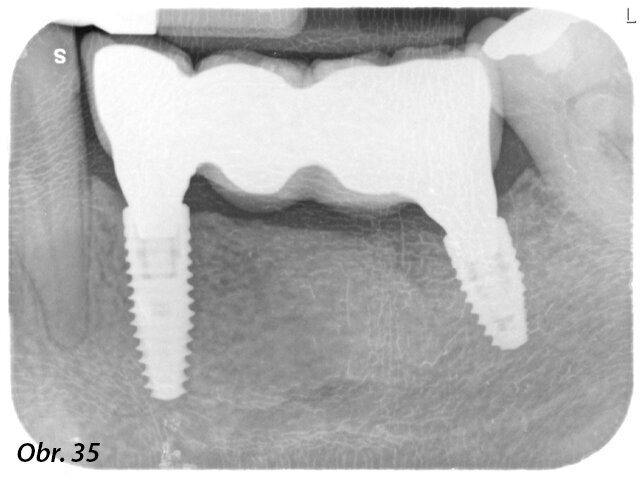

Do oblastí zubů 34 a 36 byly zavedeny dva kónické implantáty na úrovni kosti Bone Level Tapered ø 4,1 mm RC SLActive Roxolid v délce 12 mm a 8 mm (obr. 11–14).